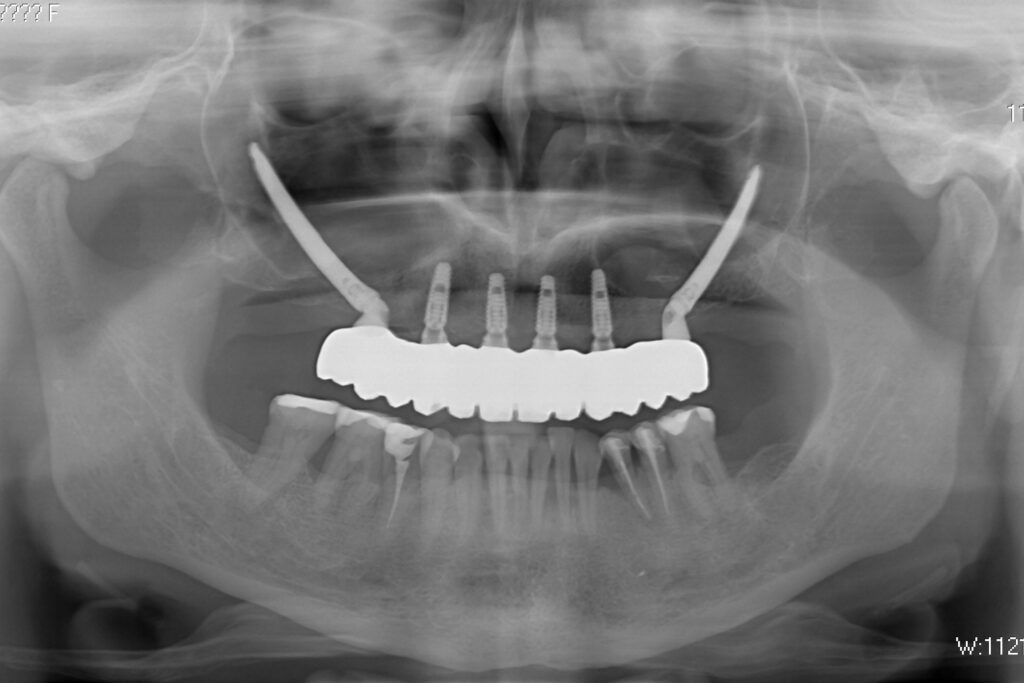

Спустя 20 дней был зафиксирован протез с опопрой на дентальные имплантаты из диоксида циркония.

процесс имплантации